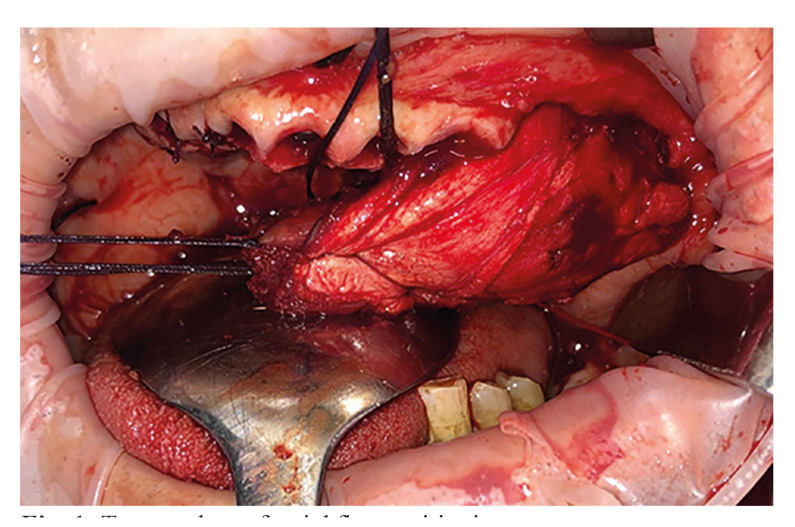

Background: Oral cavity tumours represent a global oral health issue due to their prevalence and incidence, in this paper, we will explain the procedure for the removal of various tumours and the restoration of the patient's anatomy, function and aesthetics through a novel approach that rely on a temporal muscle flap for the reconstruction of soft tissues in the surgical area.

Results: The results are shown in table 1, being the most relevant data the fact of having a series of 11 successful cases treated with temporal flap. The surgical technique involves tumor resection, preferably through an intraoral approach.